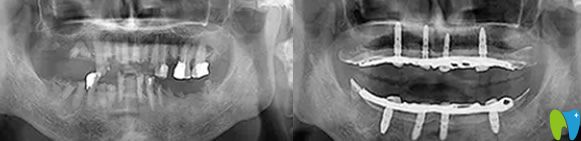

到院后,譚院長通過CT進(jìn)行數(shù)據(jù)采集,電腦精密計算人工牙根的植入位置,精準(zhǔn)制定種植方案,先把種植體種在牙槽骨內(nèi),然后再等恢復(fù)。外婆年紀(jì)大了,父母總擔(dān)心,種植過程中疼痛怕她承受不了。譚院長說我們的擔(dān)心都是多余的,會緊張那是必然的,手術(shù)是通過高氧恢復(fù),能夠讓高齡老人種牙后得到更好的調(diào)養(yǎng),真正實(shí)現(xiàn)無痛種牙。

種植前CT效果:

經(jīng)過6個月的恢復(fù)時間,來院復(fù)查,醫(yī)生說,牙槽骨和種植體緊密結(jié)合,可以為外婆裝上牙冠了,看來種植牙的成功率挺高的。術(shù)后外婆全口種植牙后的效果媲美真牙,整個人看起來也精神了好多,吃什么也更有胃口了,外婆激動的說,擁有這一口美麗的大白牙,瞬間覺得我返老還童啦!哈哈!